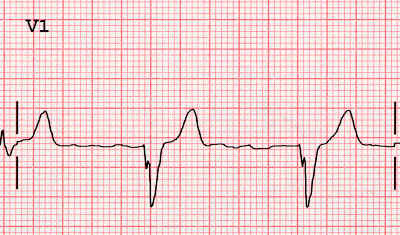

What is this and how can you tell?

Bundle branch block (wide QRS complex)